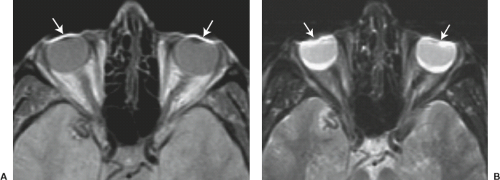

На фото артефакт от макияжа глаз из-за присутствия металлических частиц в косметических средствах.